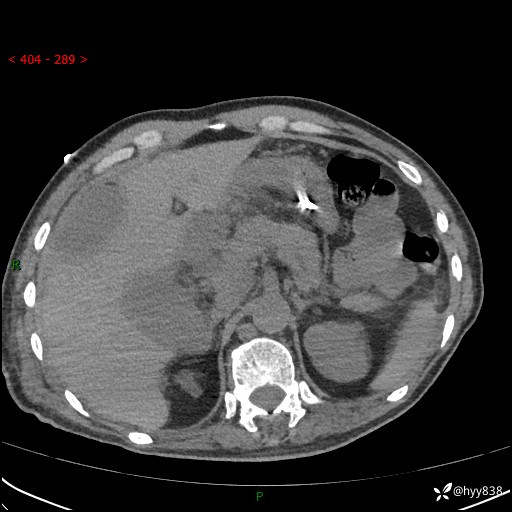

腹部CT平扫

增强